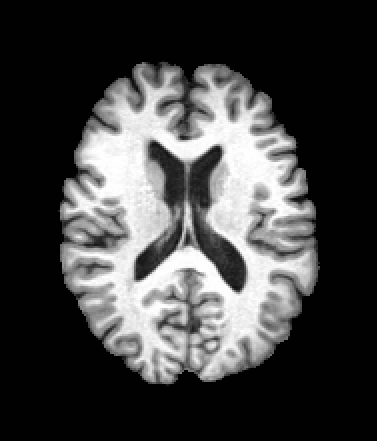

A trained MetaVoxel model can be unconditionally sampled by drawing Gaussian or categorical noise for each variable at timestep , and iteratively apply the denoising network until reaching . Unlike conventional diffusion models that focus solely on image generation, MetaVoxel can generate coherent synthetic patient profiles from the joint distribution , as shown in Figure 2.

| Age: 64.0 | Age: 53.8 | Age: 70.9 | Age: 76.9 |

| Sex: Male | Sex: Female | Sex: Female | Sex: Male |

![]() |

| Age: 80.9 | Age: 77.7 | Age: 73.2 | Age: 84.6 |

| Sex: Male | Sex: Female | Sex: Female | Sex: Female |